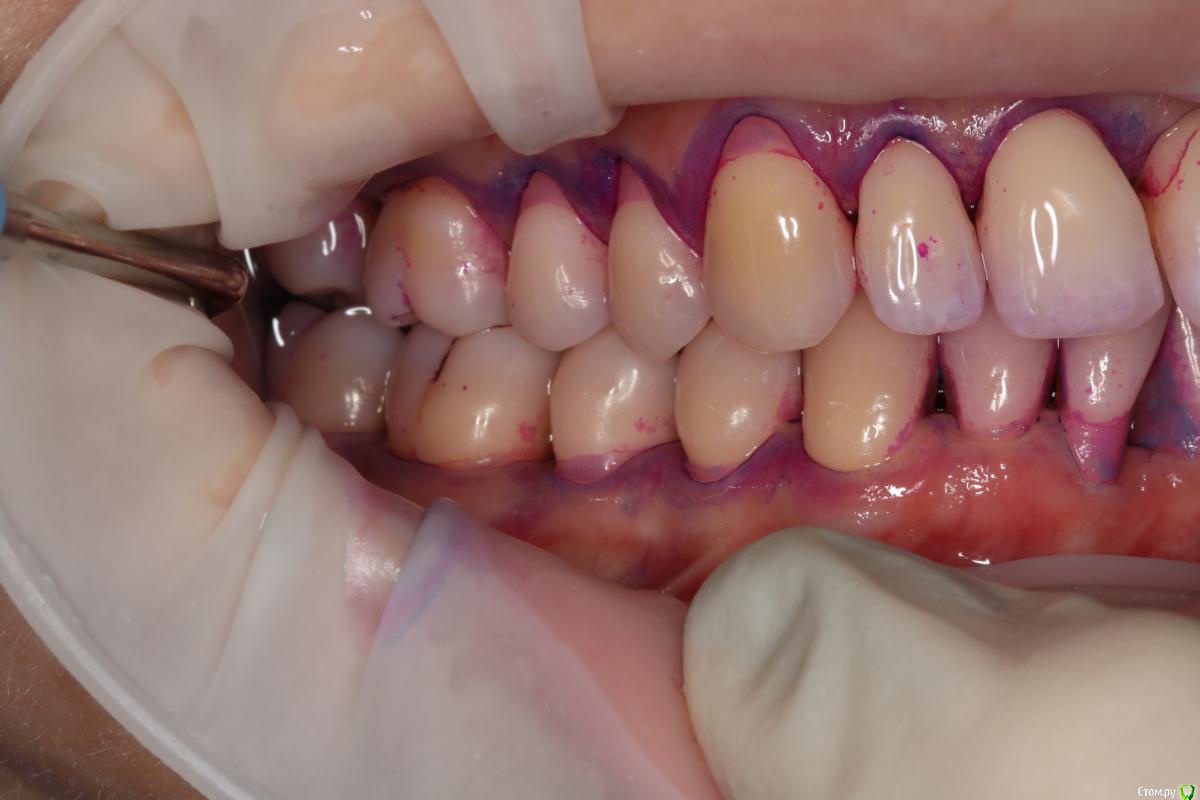

NataliaNN Опубликовано 8 ноября, 2018 Поделиться Опубликовано 8 ноября, 2018 Добрый день! У меня довольно сложная с деснами, генерализованный пародонтит, который обострился после родов и ГВ. Десны были очень воспалены, стали разворачиваться зубы. Я прошла курс чисток для лечения десен, уроки гигиены. Благодаря чему острый период воспаления прошел, сейчас состояние пародонта стабилизируется. Для дальнейшего лечения хирург планирует восстановление костной ткани на 21 и 46 зубах, и закрытие рецессий на 41, 24,25,26. А через полгода после операций можно заняться ортодонтией. Ортодонт придерживается другого мнения, сразу брекеты, а потом хирургические операции, аргументируя тем, что во время ношения брекетов результат операций может быть сведен к нулю. Хирург и ортодонт из разных клиник. Оба врача хорошие специалисты и все свои доводы аргументируют, но их точки зрения диаметрально противоположны. С чего же все-таки начать, подскажите, пожалуйста. Очень не хочется усугубить и так непростую ситуацию, к тому же все это очень затратно. Очень важно услышать мнение других специалистов. (Зубы 37,36 были потеряны в подростковом возрасте). Ссылка на комментарий

колесников Опубликовано 9 ноября, 2018 Поделиться Опубликовано 9 ноября, 2018 Не вижу смысла в ортодонтическом лечении в вашем случае (если только с 21), также сомнения в костной пластике 21,46 и в закрытии рецессии на данном этапе. Рекомендовал бы сейчас поставить импланты 36,37 с десневой пластикой , с ортопедом провести диагностику окклюзии,выявить суперконтакты,вам регулярно использовать ирригатор и через 3 мес оценить усадку десны (фронт низ-верх )и запланировать пластику рецессий. Проблема с 21 решается ортопедическим или ортодонтическим путём Ссылка на комментарий